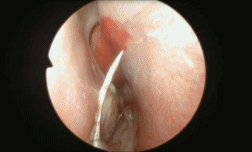

现在鼻腔手术,多数都是用鼻内镜来做。

鼻腔黏膜不像皮肤那样需要缝合,因此手术创口多为裸露,而鼻黏膜血供丰富,容易出血。

为了止血,防止血肿和脓肿发生概率,术后一般用高分子膨胀海绵“塞鼻子”。

这玩意儿遇水膨胀,并会产生一定压迫力,所以对术后鼻腔塑性和止血比较有效。02

20世纪七八十年代开始,已有学者尝试用一种“纳鞋底”(连续贯穿缝合法)的手术方法来替代鼻腔填塞。

来源:网络手术是这样“纳鞋底”

胆小勿看~

迄今已有许多国内外研究证实,这种技术相对来说痛苦小、费用低,不仅显著减少术后流泪、头部和鼻部胀痛、酸痛,最重要的是——鼻子可以立刻通畅,享受自由呼吸。